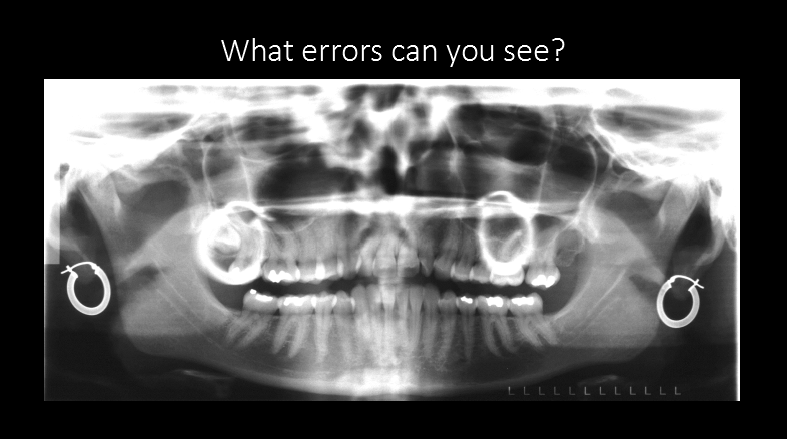

Name the errors

Palatoglossal space

earring ghost image